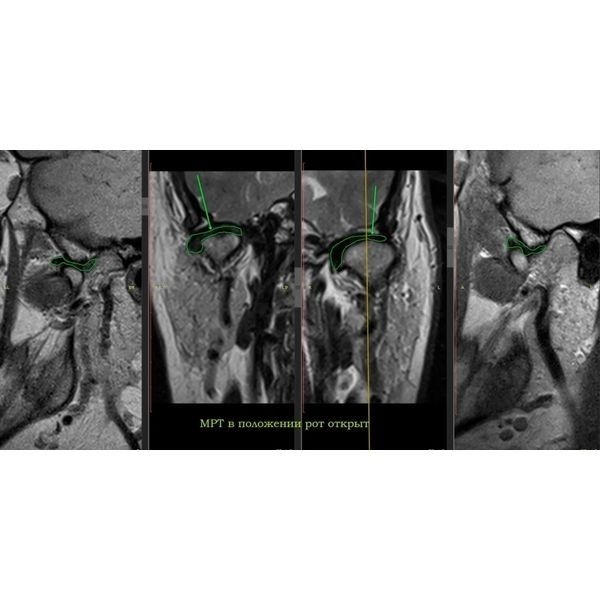

По результатам магнитно-резонансной томографии (МРТ) правого сустава:

- полное вентральное смещение суставного диска с редукцией — диск смещён вперёд, но при открытии рта суставная головка «запрыгивает» на диск;

- дистрофические изменения диска — диск начал терять эластичность и нормальную структуру;

- тенденция к перфорации промежуточной зоны диска — в средней части диска появляется риск возникновения сквозного отверстия;

- дорзальный тип установки головки мыщелкового отростка нижней челюсти — головка нижней челюсти стоит слишком далеко назад (дорзально) в суставной ямке (неправильное положение);

- остеоартроз ВНЧС 2-й степени по Kellgren — начальные дегенеративные изменения сустава.

МРТ левого сустава выявила:

- вентромедиальное смещение суставного диска с частичной редукцией — диск смещён вперёд и немного внутрь (медиально), при открывании рта он частично возвращается на место;

- компрессионный тип установки головки мыщелкового отростка — головка нижней челюсти сильно прижата к суставной ямке;

- гипермобильность головок суставных отростков — головки нижней челюсти избыточно подвижны;

- дистрофические изменения диска;

- остеоартроз ВНЧС 1-й степени по Kellgren.

При моделировании будущих зубов использовались данные аксиографии: угол суставного пути (наклон ската суставной ямки), переднюю направляющую (угол наклона центральных зубов), угол окклюзионной плоскости по сфере Монсона (высота боковых зубов). После провели примерку будущих конструкций в полости рта. Когда всё согласовали (женщина скорректировала эстетические параметры — размер и форму), конструкции зафиксировали на пару месяцев и сделали контрольное МРТ. Она показала расширение суставной щели и более корректное положение суставной головки слева.